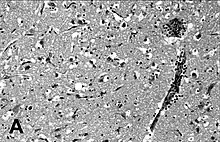

| Encephalitis in the cerebral cortex of a harbor seal with PDV, stained with hematoxylin and eosin | |